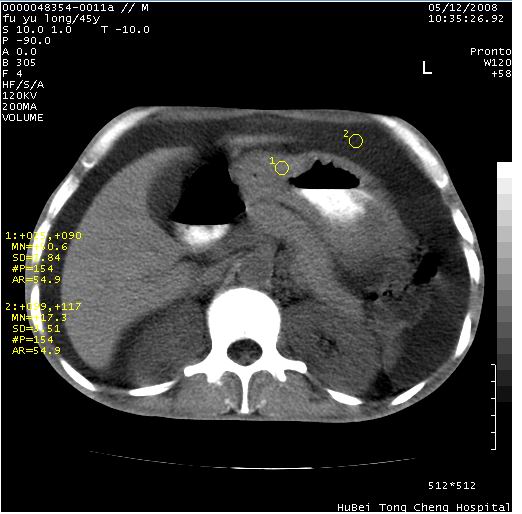

以下是引用医影拾贝在2008-5-30 2:38:00的发言:[br]气肿性胃炎、胃十二指肠溃疡、腹膜炎,考虑穿孔可能性较大

以下是引用lkc8963在2008-5-30 8:44:00的发言:[br]胃窦癌伴网膜(胃结肠韧带)/腹膜及腹膜后淋巴结转移.